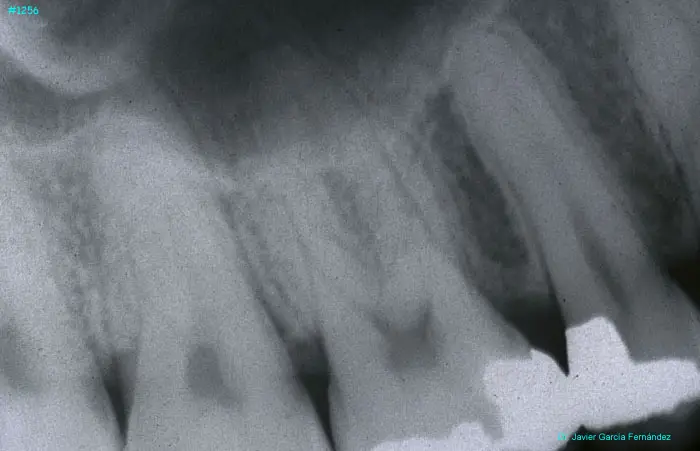

Atlas of Surgical Techniques in Periodontics. Chapter III. Atlas de Técnicas Quirúrgicas en Periodoncia